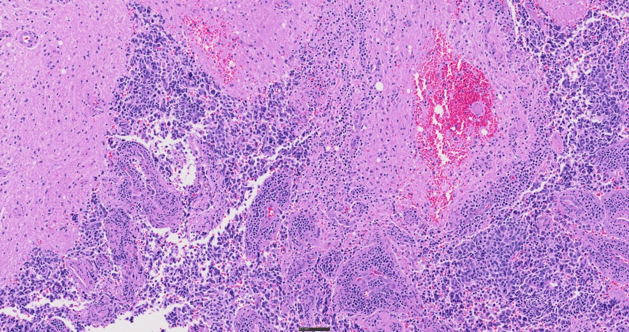

Tessuto sottoposto a colorazione H&E, 40X

Supportando fino a sei obiettivi a alte prestazioni X Line™ e integrando un'illuminazione al LED True Color oltre a dei profili per fotocamera con colori corretti, il sistema SLIDEVIEW VS200 assicura chiarezza per le immagini di vetrini interi. Lo scanner è progettato per riprodurre in modo preciso le caratteristiche dei campioni e delle colorazioni, minimizzando la necessità di ripetizione di scansioni e supportando diagnosi efficienti.

Si possono scoprire più dettagli attraverso cinque modalità di imaging (campo chiaro, polarizzazione, fluorescenza, campo scuro e contrasto di fase) e la capacità di combinare diverse tecniche in una sola scansione. Questa flessibilità offre numerose possibilità di osservare campioni istologici e citologici, dalle analisi patologiche di routine alla complessa caratterizzazione molecolare di tessuti tumorali.